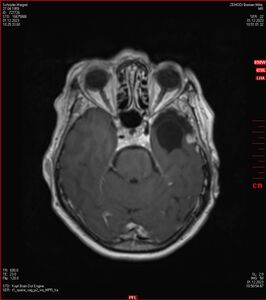

MRT vom 12. November 2024

So nun ein paar neue Bilder aus meinem Kopf. (Durch klicken bekommt man eine größe Ansicht eines Einzelbildes).

Die letzten drei Bilder Zeigen aus meiner Sicht den Tumor, der im Jahr 2021 bestrahlt wurde.

Zum Vergleich nun auch die Bilder vom 1.12.2023: